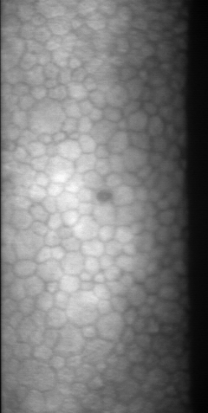

Specular microscopy assessment of the human corneal endothelium (CE) in Fuchs' dystrophy is challenging due to the presence of dark image regions called guttae. This paper proposes a UNet-based segmentation approach that requires minimal post-processing and achieves reliable CE morphometric assessment and guttae identification across all degrees of Fuchs' dystrophy. We cast the segmentation problem as a regression task of the cell and gutta signed distance maps instead of a pixel-level classification task as typically done with UNets. Compared to the conventional UNet classification approach, the distance-map regression approach converges faster in clinically relevant parameters. It also produces morphometric parameters that agree with the manually-segmented ground-truth data, namely the average cell density difference of -41.9 cells/mm2 (95% confidence interval (CI) [-306.2, 222.5]) and the average difference of mean cell area of 14.8 um2 (95% CI [-41.9, 71.5]). These results suggest a promising alternative for CE assessment.